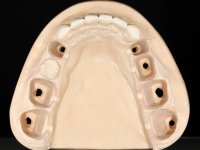

Realizado o diagnóstico e tomada a decisão quanto ao tratamento a executar, tornou-se importante definir qual a sequência de trabalho a adotar no sentido de conseguir a reabilitação da D.V.O. (V.D.O), de forma progressiva e equilibrada. Na primeira fase fez-se uma pré-impressão da arcada inferior com silicone tipo “putty” e em seguida realizou-se o preparo dentário de todo o sector posterior. O preparo para os overlays foi feito coronalmente à linha amelo cementaria no sentido de ser o mais conservador possível. A impressão foi feita com técnica de dupla mistura após afastamento gengival realizado com pasta de caulino. A provisória foi realizada com resina composta de polimerização dual. Em laboratório foram realizados os overlays após se ter aberto ligeiramente (1,5mm) a D.V.O. nos modelos montados em articulador semi-ajustável. Simultaneamente o sector antero-inferior foi encerado no sentido de acompanhar este aumento da D.V.O. Também foi confecionada uma chave de silicone translucido para posterior confeção dos provisórios antero-inferiores. Em boca foi primeiro realizada a provisionalização dos dentes anteriores utilizando resina composta previamente aquecida após preparação das superfícies dentárias para a adesão. Foi colocado o dique de borracha para promover o isolamento absoluto e posteriormente foram colados os overlays. Em laboratório foi realizada nova chave de silicone para confecionar os provisórios antero-superiores. Seguidamente em boca foram preparados os seis dentes antero-superiores após colocação do fio de afastamento gengival. Feita a preparação adequada das superfícies dentárias foi realizada a impressão com técnica de dupla mistura e a respetiva provisória. Em laboratório foram confecionadas 6 facetas feldespáticas num modelo de trabalho tipo “Geller”. A provisória foi removida e as facetas foram coladas em boca utilizando um isolamento relativo competente. Esta opção foi tomada em virtude de uma prévia experiencia negativa com a colocação do dique de borracha na mandibula. Após a colagem dos laminados antero-superiores foram dadas 12 semanas para avaliar a adaptação do paciente à nova situação e então iniciar a confeção das facetas antero-inferiores. Após colocação do fio de afastamento gengival. foram feitos os preparos dentários adequados e em seguida foi feita a impressão. Também foi feita a preparação do dente 3.4 que, entretanto, tinha sofrido uma fratura do overlay. As facetas e a restauração do 3.4 foram realizadas num modelo de trabalho tipo “Geller”. Após remoção da provisória, as facetas foram coladas em boca, utilizando um isolamento relativo pelas razões apontadas anteriormente. Após colocação do trabalho o paciente foi reabilitado por outros colegas com um implante na zona do 2.6 e substituição da coroa aparafusada sobre o implante colocado no local do 3.5. Posteriormente surgiram fraturas nos overlays dos dentes 4.7 e 3.7 que foram reabilitados com overlays em Zr.